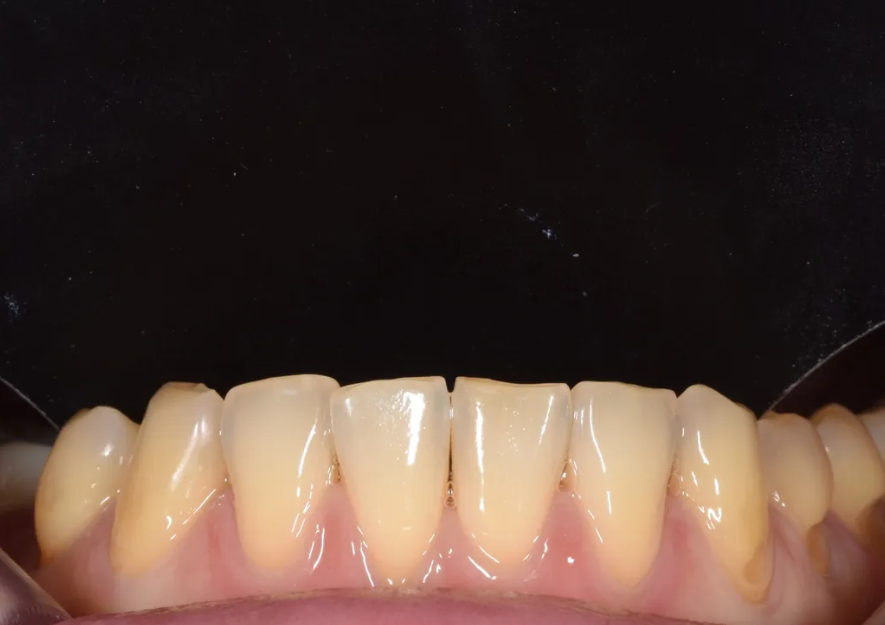

아랫니 앞니 부분의 문제점

오른쪽 앞니 부분 삐뚤어짐, 가운데 앞니 벌어짐

아랫니 쪽도 문제가 여럿 있었습니다. 오른쪽 앞니 두 개가 살짝 삐뚤어져 있었고, 가운데 아랫 앞니 사이에는 벌어진 공간이 있었습니다. 왼쪽 송곳니부터 두번째 작은어금니까지는 잇몸 경계 부위가 마모(치경부 마모)되어 있는 상태였습니다.

이 외에도 위아래 정중선(치아 가운데 라인)이 서로 일치하지 않았고, 위아래 앞니의 교합이 상당히 긴밀한 상태여서 이 역시 치료 시 고려가 필요했습니다.